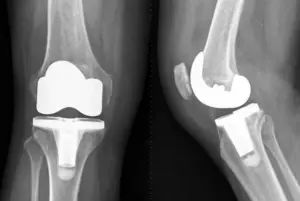

Knee X-ray image after a total knee replacement operation. The diseased knee joint is replaced with artificial material (White parts). Frontal view and side-view.